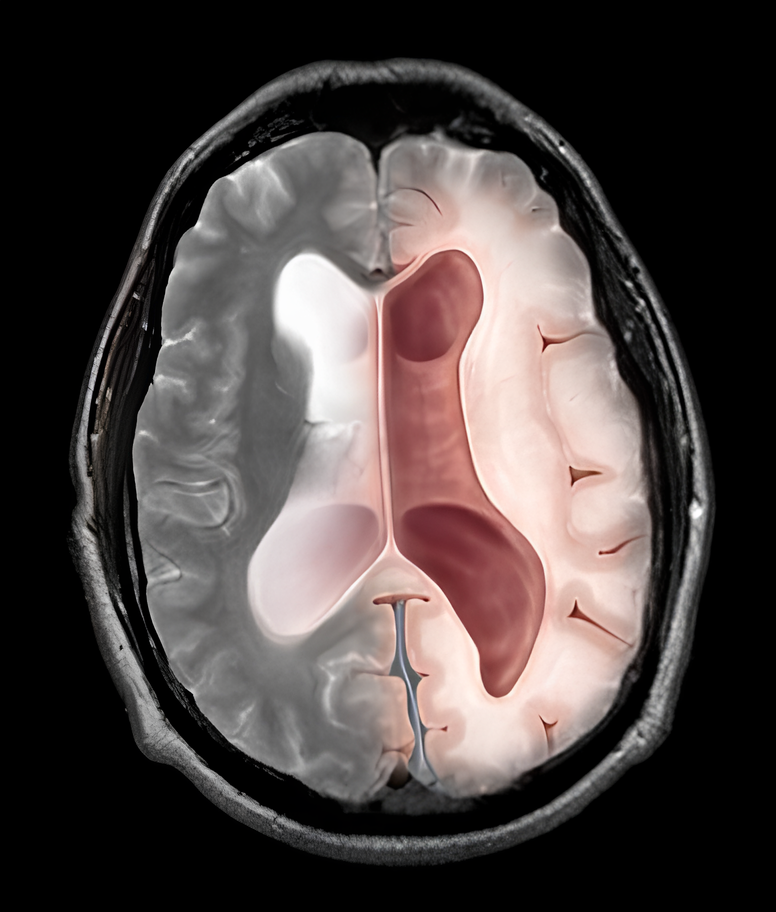

Hình 2. Tam chứng Hakim ở bênh nhân giãn não thất áp lực bình thường (NPH) với rối loạn dáng đi, tiểu không tự chủ, sa sút trí tuệ (A) và mô phỏng não thất giãn với áp lực bình thường ở bênh nhân lớn tuổi (B).

Bệnh xảy ra khi sự hấp thu dịch não tủy tại khoang dưới nhện bị rối loạn, gây ứ đọng trong não thất, làm giãn hệ thống não thất và chèn ép các cấu trúc quanh não thất – đặc biệt là sợi thần kinh vùng trán và thể chai liên quan đến điều hòa vận động và nhận thức.